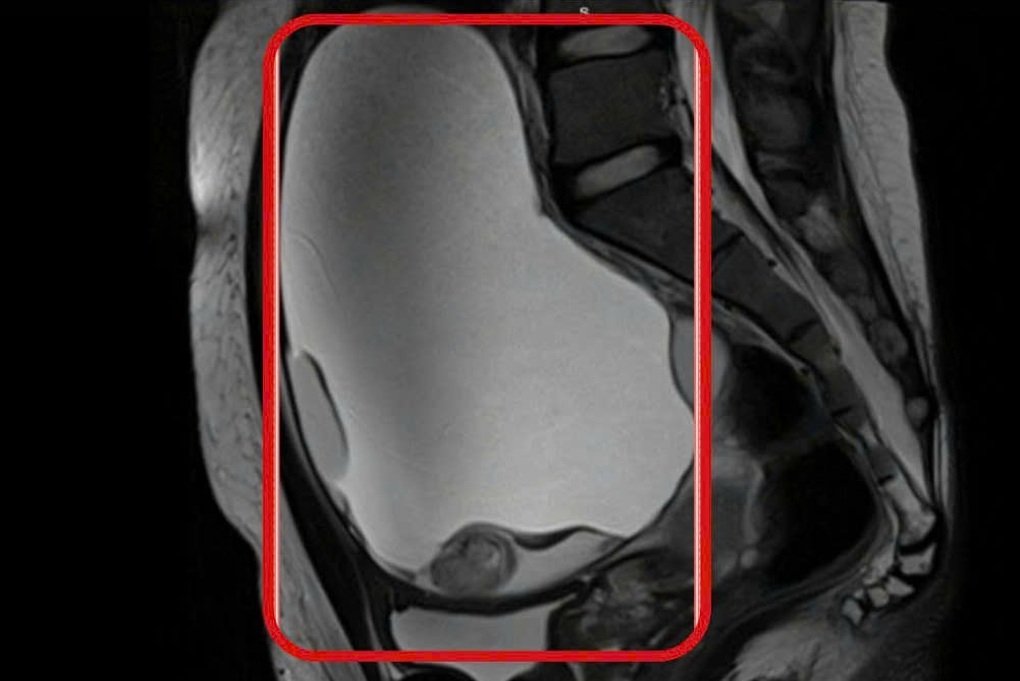

Qua thăm khám lâm sàng, các bác sĩ nhận định đây là tình trạng đau bụng bất thường trên nền thai lớn, tiềm ẩn nhiều biến chứng. Bệnh nhân được hội chẩn đa chuyên khoa và chỉ định chụp MRI, ghi nhận khối u buồng trứng phải bị xoắn, kích thước 6x8cm, phải phẫu thuật khẩn cấp.

Qua thăm khám lâm sàng, các bác sĩ ghi nhận vùng hạ vị của cô gái có khối căng lớn (17x18cm), di động và đau rõ khi chạm. Kết quả MRI cho thấy hai buồng trứng của bệnh nhân đều có khối u lớn choán chỗ, bên trong chứa dịch, mỡ và vôi hóa.